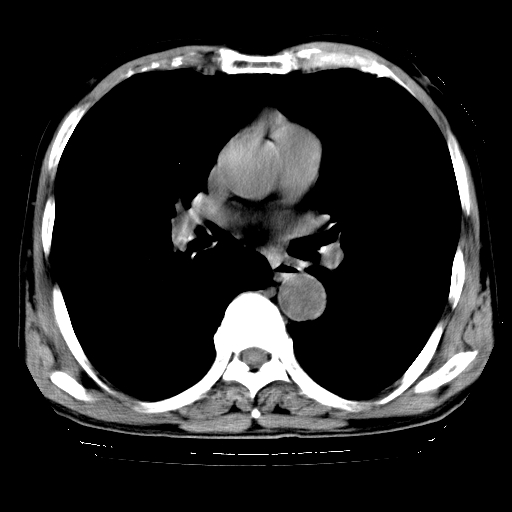

以下是引用hhcckk在2009-1-1 15:38:00的发言:[br]左下肺少许絮状模糊影--考虑感染[br]两肺散在小点状密度增高影--结合病史考虑矽肺?[br]气管壁钙化--可能由于老年退变性引起的